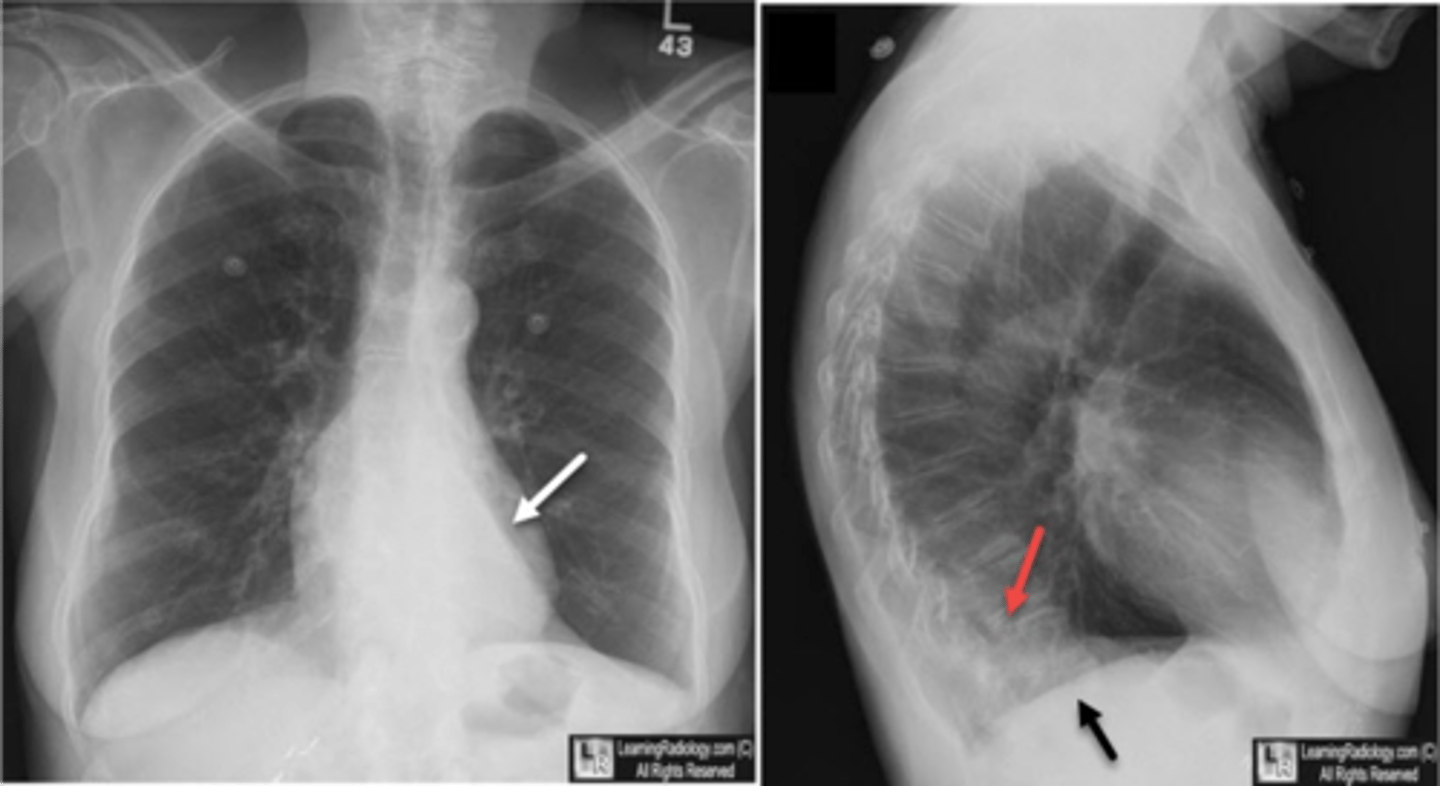

Flattening of hemidiaphragms

& blunting of costophrenic angles, Increased AP diameter (barrel chest), bullae or large air cavities indicates

hyperinflation

COPD/Emphysema

knowt flashcard image